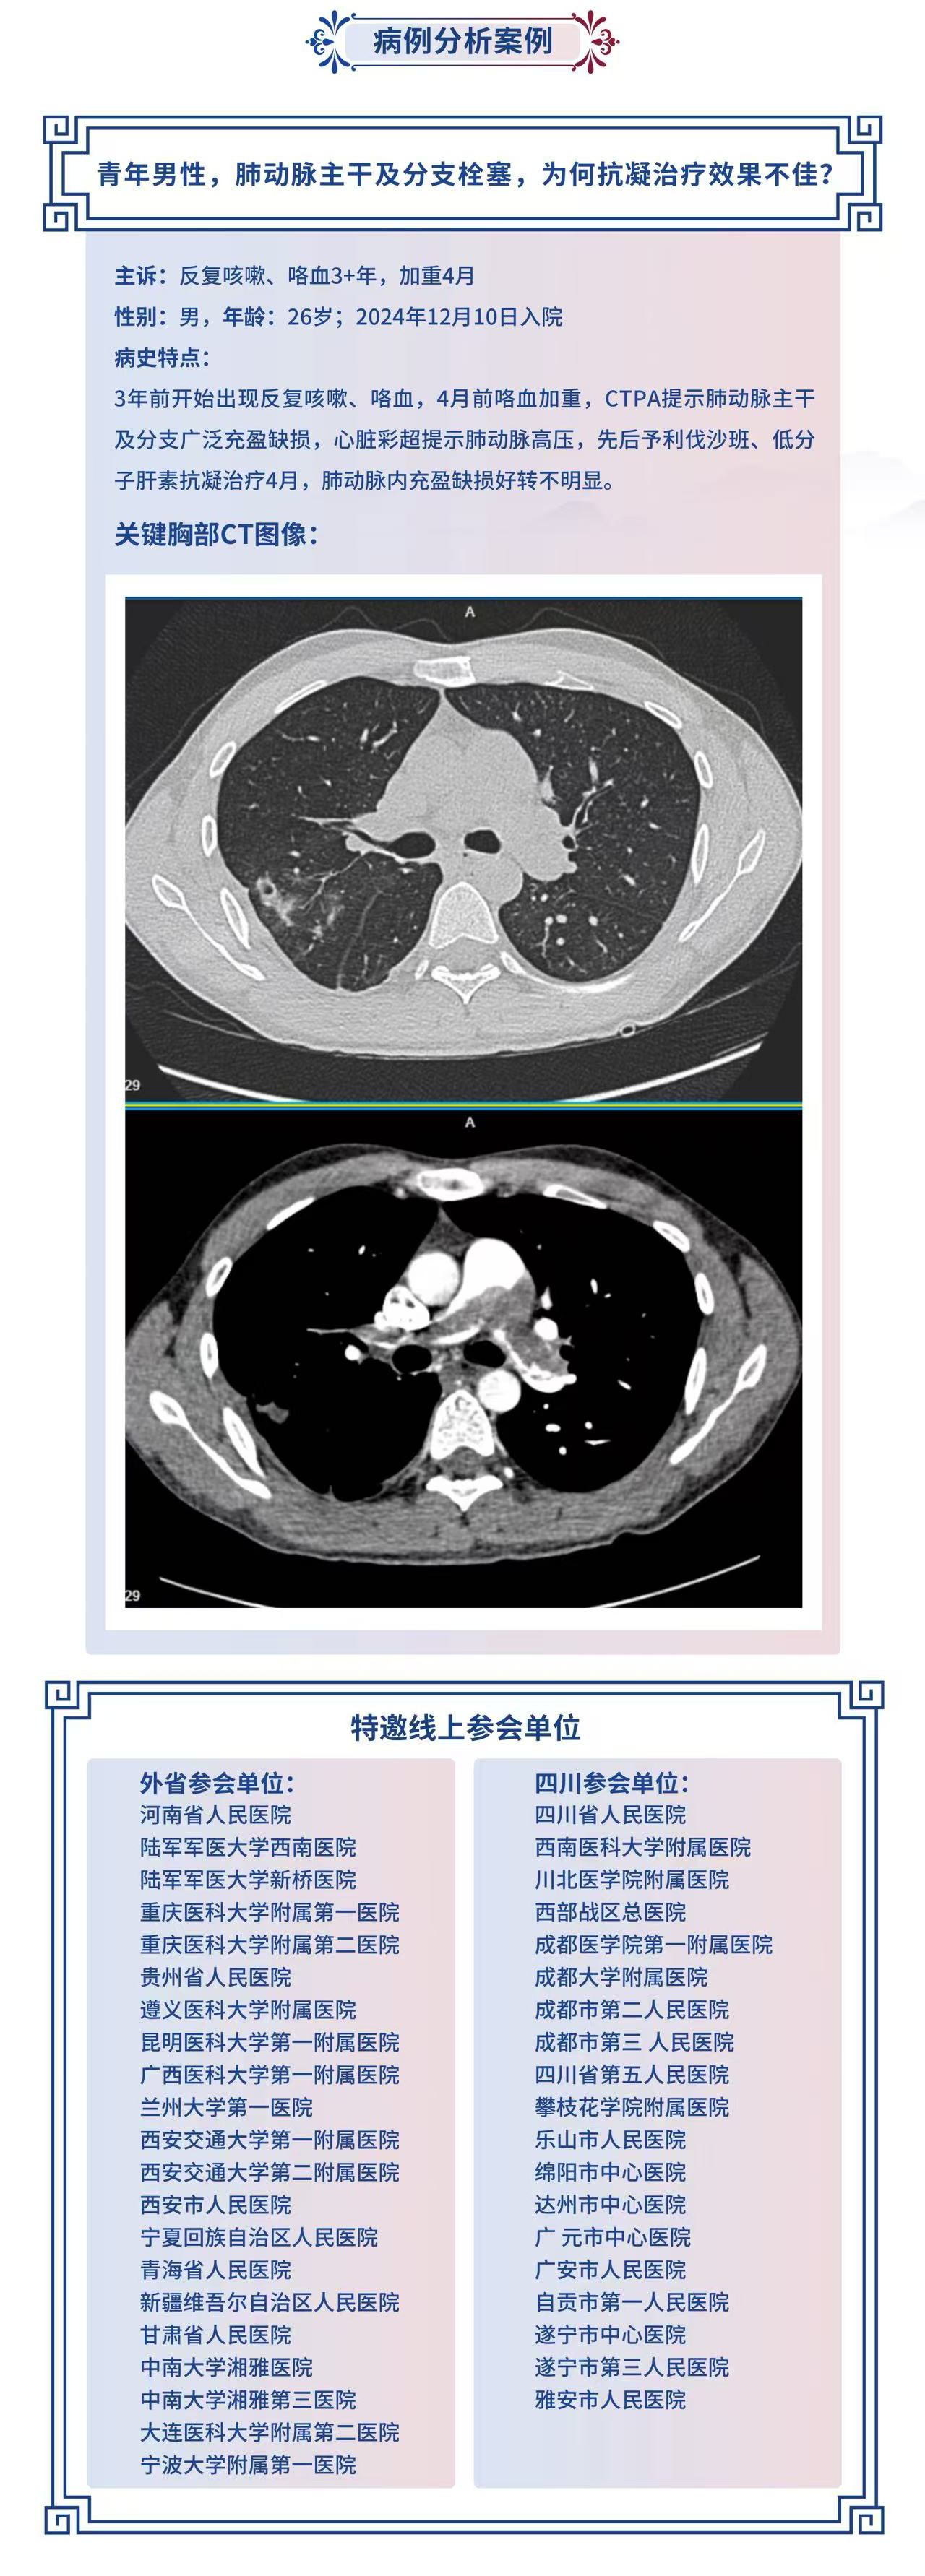

壹生直播青年男性,肺动脉主干及分支栓塞,为何抗凝治疗效果不佳?【华西呼吸在线(第49期)】

青年男性,肺动脉主干及分支栓塞,为何抗凝治疗效果不佳?【华西呼吸在线(第49期)】